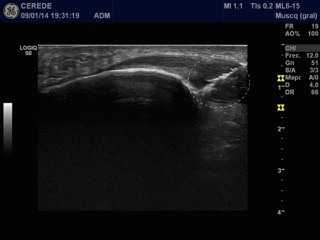

Figure 3 Hiperecoic image produced by the EPI® needle of 0,30mm in the degenerative area of the tendon. This hiperecoic image corresponded to a gas density produced by the electrochemical response of the catodic flow (CF) in the degenerative extracellular matrix.

Figure 4 Ultrasound image in longitudinal view and colour Doppler two week after the EPI® technique treatment ultrasound-guided. It is observed the degenerated area of the tendon that is substituted by a new connective tissue and decrease the neovascular effect.